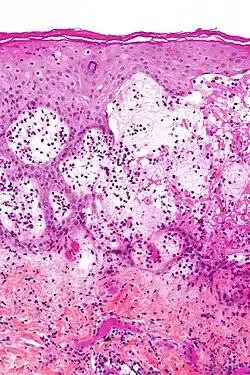

| Micrografia do penfigoide gestacional com as bolhas sub-epidérmicas características e eosinófilos abundantes. | |

Penfigóide gestacional é uma dermatose da gravidez. É uma doença autoimune e bolhosa da pele que ocorre durante a gravidez, geralmente no segundo ou terceiro trimestre e/ou imediatamente após o nascimento. Era inicialmente denominada herpes gestacional devido à aparência semelhante, embora não tenha nenhuma associação com o herpesvírus.[1][2][3]